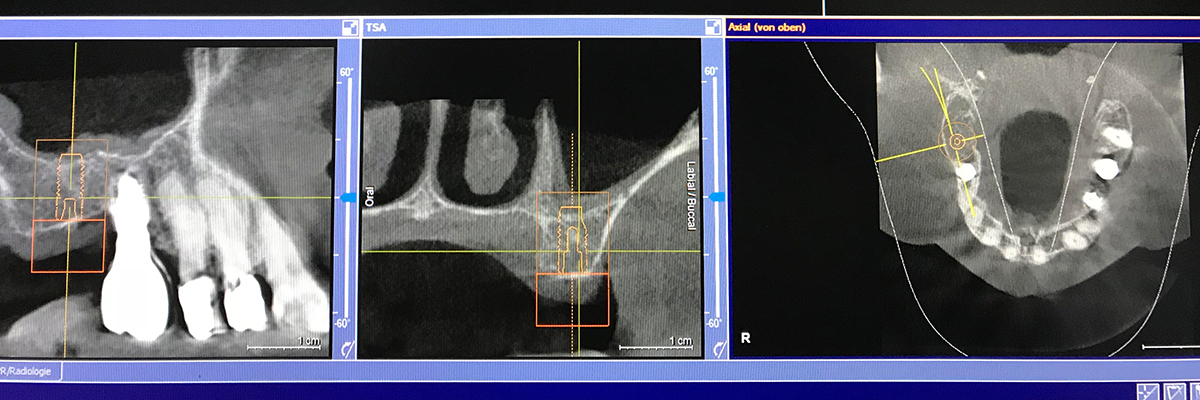

Dabei handelt es sich um ein hochauflösendes, bildgebendes Verfahren, das eine präzise und kontrastreiche dreidimensionale Diagnostik ermöglicht.

Ihr Vorteil: Es wird ein dreidimensionaler Blick in das Innere des Knochens, der Zähne und der Nachbarstrukturen bei geringer Strahlenbelastung möglich. Ein minimal-invasiver und maximal-schonender Eingriff ist planbar.

- Implantate: Durch das Anfertigen dreidimensionaler Querschnittbilder, die sämtliche anatomische Strukturen wie den Unterkiefernerv, das Knochenvolumen zeigen, ist es uns möglich, mit den Aufnahmen die Behandlungsschritte zu simulieren und mögliche Behandlungsergebnisse darzustellen. So können wir für Sie die optimale Therapievariante auswählen. Wir legen die Position eines Implantats im Vorfeld fest und fertigen eine passgenaue Bohrschablone für die Implantat-OP an.